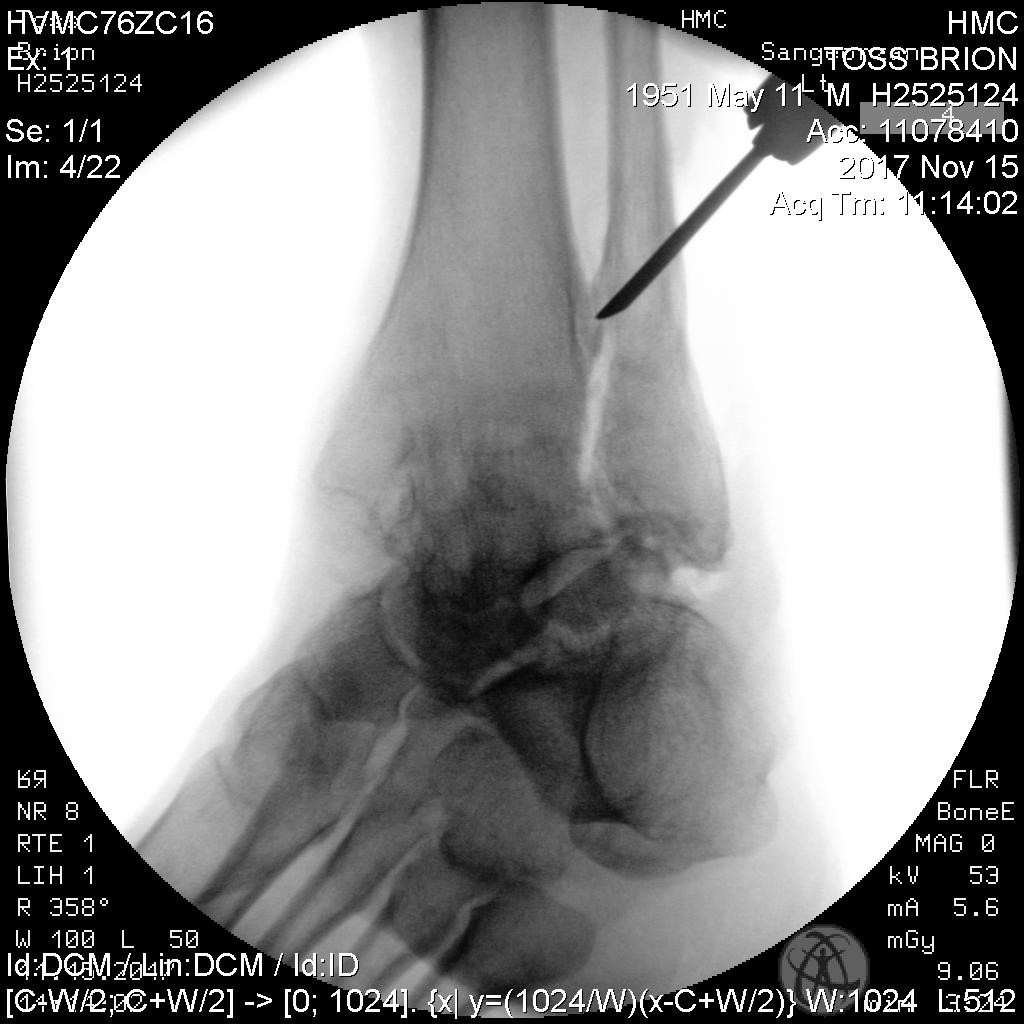

What is a mortise and tenon joint and what is it used for? Mortise and tenon A mortise and tendon joint – brion toss yacht riggers

A Mortise and Tendon Joint – Brion Toss Yacht Riggers